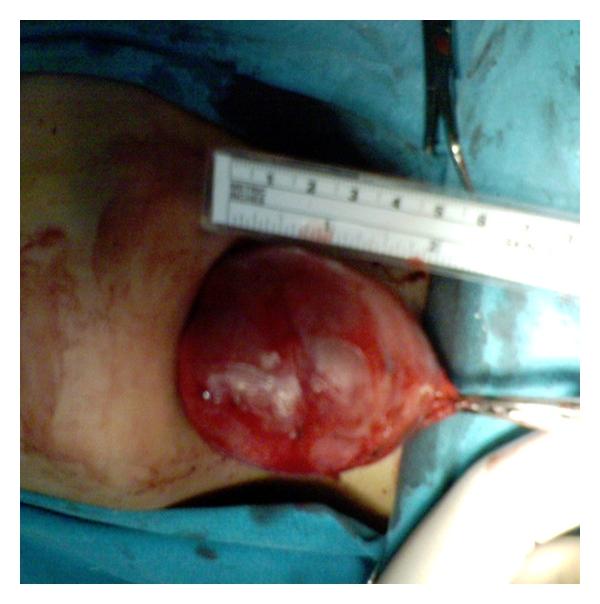

Dermoid cysts in the floor of the mouth may be congenital or acquired. The congenital form, according to the main theory, originates from embryonic cells of the 1st and 2nd branchial arch. The acquired form may be due to traumatic or iatrogenic causes and as a result of the occlusion of a sebaceous gland duct. Its occurrence is less and is estimated to be from 1.6 to 6.4% of the dermoid cysts of the body in adults and 0.29% of the head and neck tumors occurring in children. They may also be classified as anatomical and histological. Anatomically, they are divided into median genioglossal, median geniohyoid, and lateral cysts, while histologically they are divided into epidermoid, dermoid cysts and teratomas. Clinically, a distinction between supra and inferior type as well as between central and lateral type is proposed in relation to themylohyoidmuscle and themidline, respectively. Histologically, an estimation of dermoid, epidermoid, and teratoid cysts is reported. Enucleation via intraoral and/or extraoral approach is the method of treatment. Two case reports of dermoid cysts in the floor of the mouth are presented in this paper, and an evaluation with regard to pathology, clinical findings, differential diagnosis, and treatment is discussed.

口腔底部的皮样囊肿可能是先天性的或后天获得性的。根据主要理论,先天性皮样囊肿起源于第一和第二鳃弓的胚胎细胞。后天获得性皮样囊肿可能是由创伤或医源性原因引起的,也可能是皮脂腺导管阻塞的结果。其发生率较低,据估计,在成人体表皮样囊肿中占1.6%至6.4%,在儿童头颈部肿瘤中占0.29%。它们也可按解剖学和组织学进行分类。在解剖学上,它们分为正中颏舌肌型、正中颏舌骨型和外侧囊肿型,而在组织学上,它们分为表皮样囊肿、皮样囊肿和畸胎瘤。临床上,分别根据下颌舌骨肌和中线提出了上型和下型以及中央型和外侧型的区分。在组织学上,报告了皮样囊肿、表皮样囊肿和畸胎样囊肿的评估情况。通过口内和/或口外入路摘除是治疗方法。本文介绍了两例口腔底部皮样囊肿的病例报告,并讨论了病理学、临床发现、鉴别诊断和治疗方面的评估情况。